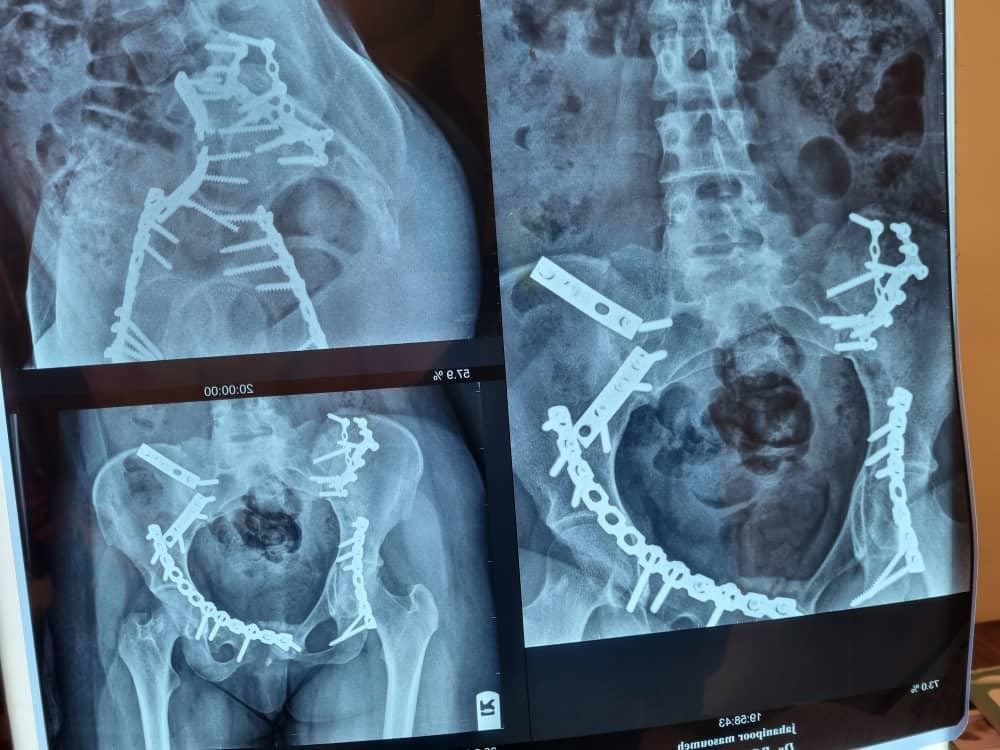

جراح و متخصص ارتوپدی

ژنرال ارتوپدی سابقه ۲۶ سال

*جراحی ارتوپد

*بازسازی شکستگی های لگن و مفصل ران (هیپ) آرتروپلاستی زانو آرتروسکوپی هیپ و زانو

*اصلاح بد جوش خوردگی

*جوش نخوردگی های استخوانی